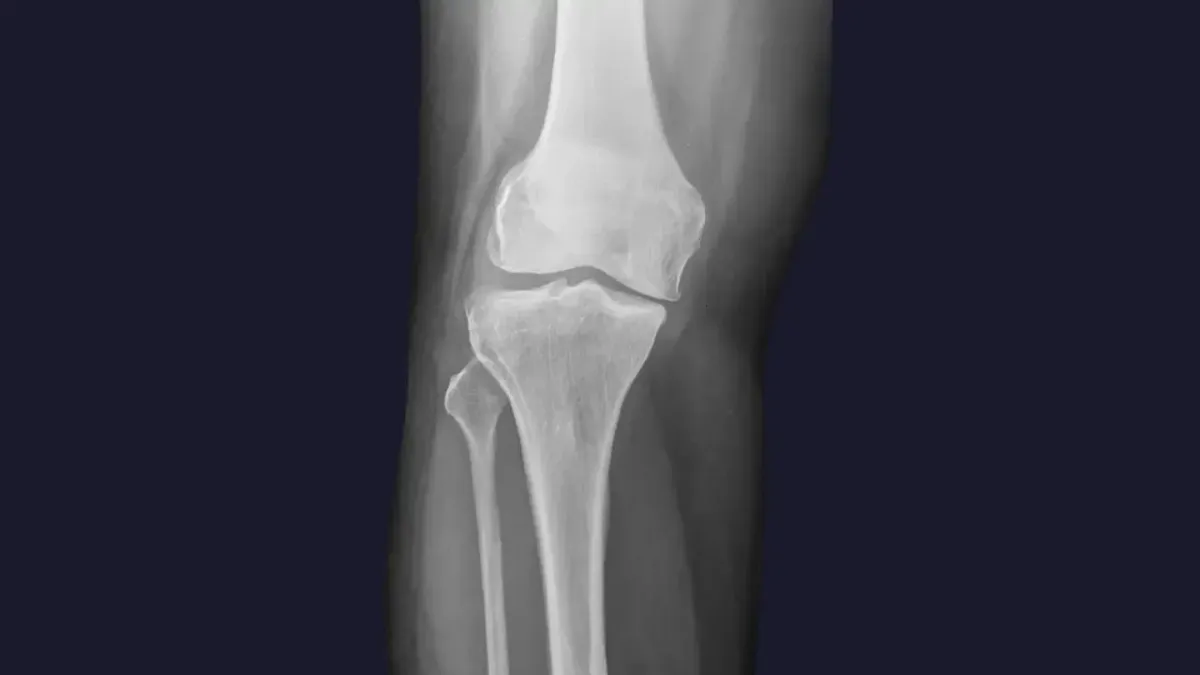

Knee pain is a widespread complaint, often stemming from a variety of sources. Here are some of the common culprits we see in Lawrenceville, GA :

Misalignment: Even subtle misalignments in the knee joint itself, or in the hips and pelvis, can lead to improper tracking of the kneecap, increased wear and tear, and pain.

Arthritis: Degenerative changes in the knee joint can cause stiffness, swelling, and chronic pain.

Ligament or Meniscus Issues: While severe tears may require surgical intervention, chiropractic care can help manage pain and improve function for less severe injuries by optimizing joint mechanics and supporting the healing process.

Poor Biomechanics: Imbalances in the muscles surrounding the knee, or issues with foot mechanics, can place excessive stress on the joint.